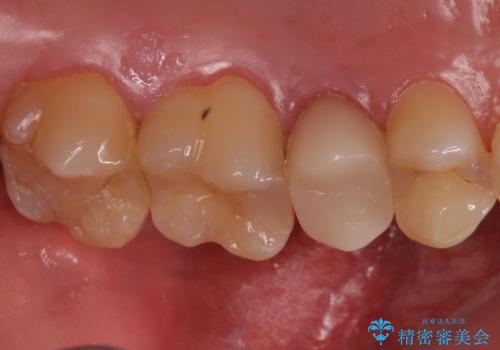

- 左上の歯茎にできものができたとのことで来院された患者様です。

術前検査より根管内の感染が疑われたため、再根管治療を行います。

根管内の感染源を可能な限り除去し洗浄しました。